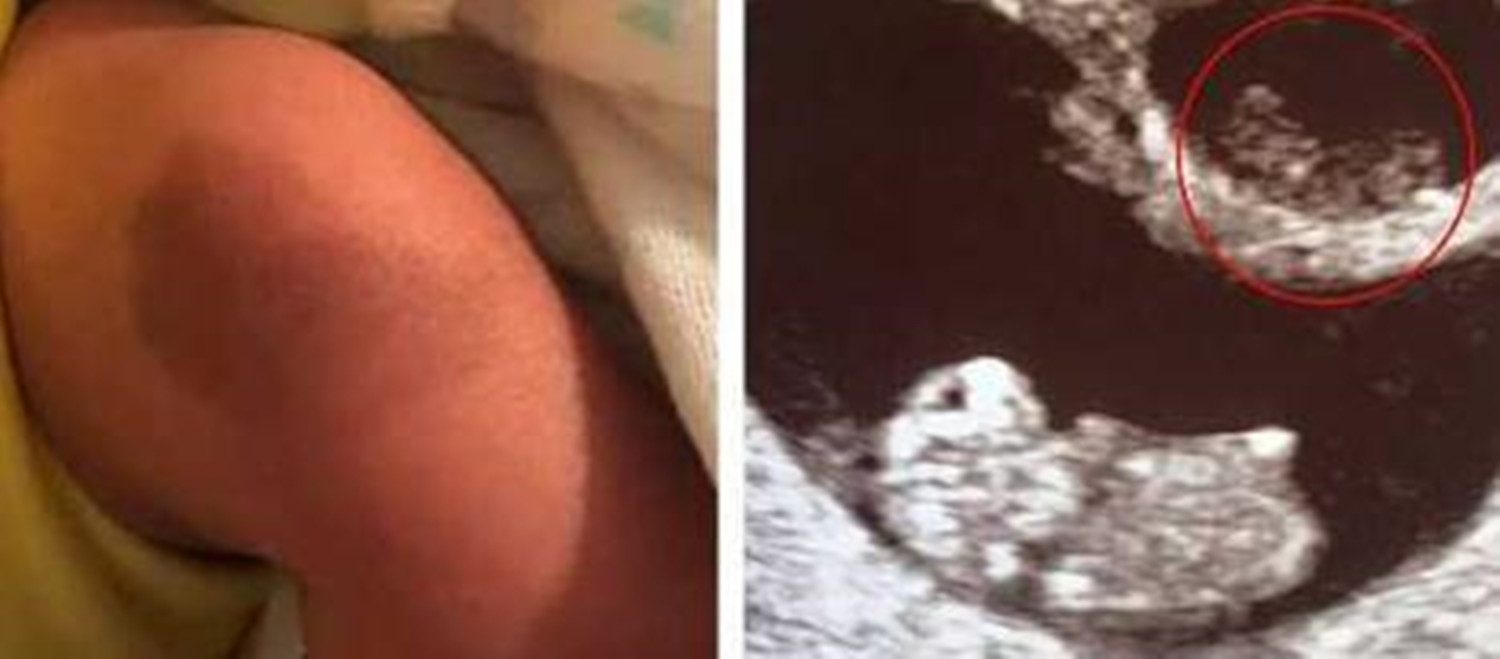

据《每日邮报》2月11日的报道,一名叫吉文斯的美国女子于今年初产下的儿子,腿上膝盖处存在一块胎记。

这块胎记有什么值得称奇的呢?原因在于其形状,与新生儿的龙凤胎姐姐孕期拍下的B超影像高度相似,下面跟大家说说细节。

好在最后龙凤胎中的弟弟健康降生了,更令她惊喜的是,当护士抱着孩子到她跟前时,还特地指了这块腰果状胎记给她看,形状和被“吸收”的姐姐的B超影像十分相似。

吉文斯既惊讶,又感觉得到了慰藉,心想这可能是未出生的姐姐给弟弟留下的一种特殊回忆吧。

弟弟出生后腿上的这块胎记,引发了众多关注,对这种奇妙的巧合,网友评论道: